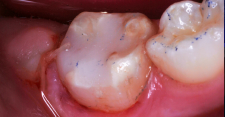

A 7-year-old boy had a newly erupted mandibular right permanent first molar. The tooth had hypoplastic and hypocalcification malformation and associated dental caries (Figure 14). After inferior alveolar block anesthetic injection, the rubber dam was applied using the slit-dam method.8 Occlusal-distobuccal preparation was completed using a water-cooled, coarse-grit cylindrical diamond bur. All carious and chalky hypocalcified tooth structure was removed. Preparation design included mechanical undercut retention form (Figure 15).  After placement of an orthodontic band as a matrix, without removal of the rubber dam clamp, 5% glutaraldehyde/HEMA desensitizing solution was applied and agitated with a microbrush for two 60-second exposures, and air-dried after each application (Figure 16). A self-etching bonding agent was then painted over the enamel and dentin and spread to a thin layer with the air syringe. After 10 seconds of light exposure, an RMGI bioactive ionic resin-based composite was injected to overfill, in one portion. The restoration was trimmed with slow-speed diamond burs, and the self-etching bonding agent was applied over the composite surfaces and surrounding enamel. The light beam was applied for another 10 seconds (Figure 17).  Occlusion was determined using articulating paper, and corrections were made (Figure 18). The occlusal view of the restored molar is shown 20 months after treatment (Figure 19).

Finished RMGI bioactive ionic resin-based composite restoration.

Figure 18

Occlusal view

Figure 19